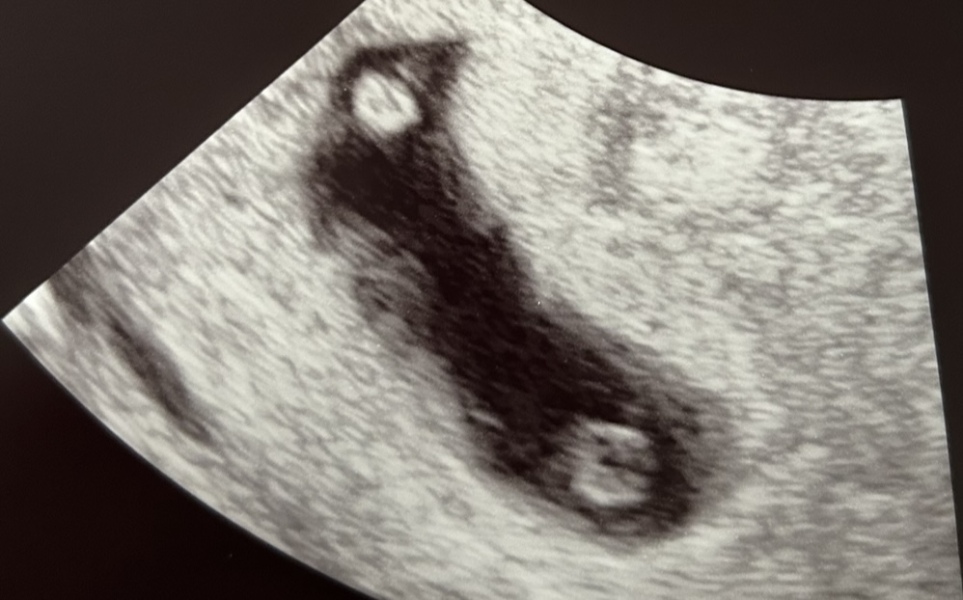

Jewellerycookiesandcream · 27/06/2024 20:20

I’m current pregnant with mono di twins (identical) and had an early scan at 7 weeks ( attached). In my case the sonographer could tell straight away they were twins and also that they were sharing a placenta so were mono di. Xx